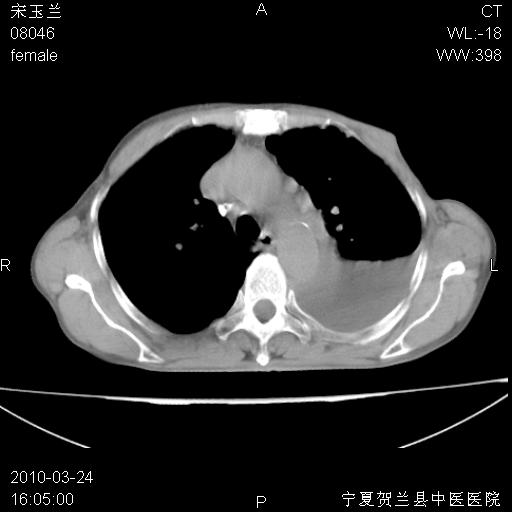

以下是引用zxl51642在2010-3-24 18:49:00的发言:[br]结合乳腺癌术后病史,考虑双肺及纵隔淋巴结多发转移、左侧胸膜转移并左侧大量胸水、左下肺膨胀不全。